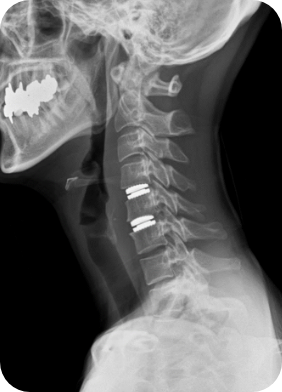

Artificial Disc

Replacement

경추 인공디스크치환술

경추 인공디스크란 목디스크 환자에게서 수술후에도 분절간 운동 범위를 유지 하기 위해 시행하며, 손상된 디스크를 제거 후 이식하는 뼈 대신 인공디스크를 삽입하는 치료법입니다.

수술 후 정상 기능을 최대한 보존하며 목도 자유롭게 움직일 수 있는 장점이 있습니다.

피부를 최소절개한 후 신경을 누르고 있는 디스크를 제거한 뒤 인공디스크를 삽입하게 됩니다.

척추유합술과 수술법은 유사하나 인체 디스크와 유사한 인공디스크를 삽입하는 방법의 치료입니다.